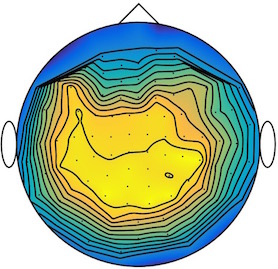

We applied our method to a magnetoencephalography (MEG) dataset. In this setup, brain activity of a subject is recorded (Elekta Neuromag, 306 sensors of which 204 planar gradiometers and 102 magnetometers, sampling frequency 1000Hz) while the subject reacted to the presentation of a target stimulus by pressing either the left or the right button.

Data is preprocessed applying signal space separation correction, interpolation of noisy sensors, and realignment of data into a subject-specific head position (MaxFilter, Elekta Neuromag). The signal was then filtered (low pass 40HZ), and artifacts such as blinks and heartbeats removed thanks to Signal-Space Projection using the Brainstorm software222http://neuroimage.usc.edu/brainstorm. The samples we used for our barycenter computations are an average of the norm of the two gradiometers for each channel from stimulation onto 50ms and the classes were left or right button.

| Class 1 | Class 2 | ||||||

|

|

|

|

|

|

|

|

| Sample 1 | Sample 2 | Sample 3 | Mean | Sample 1 | Sample 2 | Sample 3 | Mean |

|

|

|

|

|

|

|

|

This results in two classes of recordings, one for each pressed button. We aim at computing a representative activity map for each class using Wasserstein barycenters. For each class we have recordings each having samples located on the vertices of an hexahedral mesh of a hemisphere (corresponding to a MEG recording helmet). These recorded values are positive by construction, and we rescale them linearly to impose . Figure 6, top row, shows some samples from this dataset, displayed using interpolated colors as well as iso-level curves. The black dots represent the position of the electrodes on the half-sphere of the helmet, flattened on a 2-D disk.

We computed TV-regularized barycenters independently for each class by solving (16) with the TV regularization using the projected gradient descent method (22). We used a squared Euclidean metric (24) on the flattened hemisphere. Since the data is defined on an irregular graph, instead of (23), we use a graph-based discrete gradient. We denote the graph which connects neighboring electrodes. The gradient operator on the graph is

The total variation on this graph is then obtained by using , the norm, i.e. we use in (23).

Figure 6 compares the naive barycenters (i.e. the usual mean), barycenters obtained without regularization (i.e. ) and barycenters computed with an increasing regularization strength . The input histograms being very noisy, the use of regularization is important to make the area of significant activity emerge from the noise. The use of a TV regularization helps to keep a sharp transition between active and non-active regions.